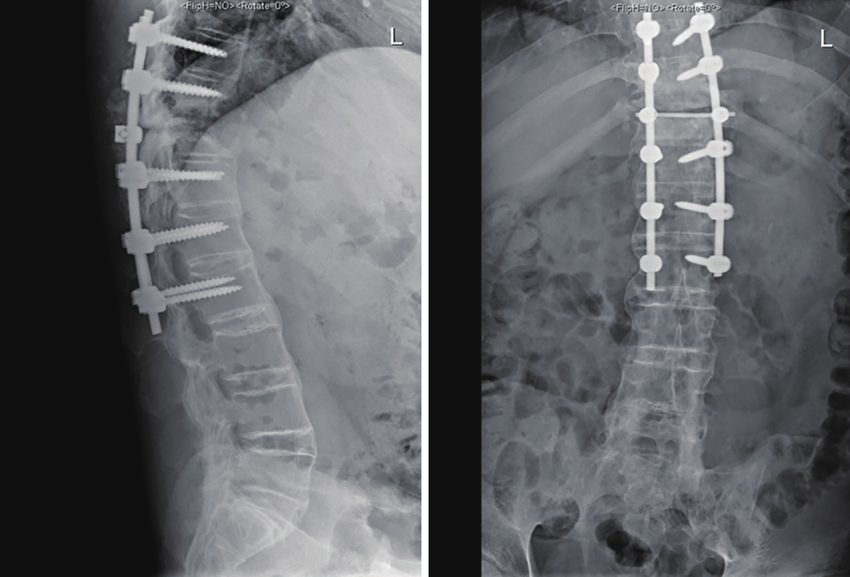

At Summit Orthopaedic Hospital , we believe in holistic management of spine related problems. All surgeries related to cervical, dorsal or lumbar spine are performed at our institution. Surgeries related to vertebral fractures, infections, disc lesions, spinal canal stenosis, deformity correction are performed at our hospital.

Pain management procedures related to spine problems like vertebroplasty, kyphoplasty, transforaminal injections, facet joint blocks, nerve root blocks are available. Facilities for minimally invasive spine surgery (MISS) and endoscopic spine surgery are also available at our hospital.